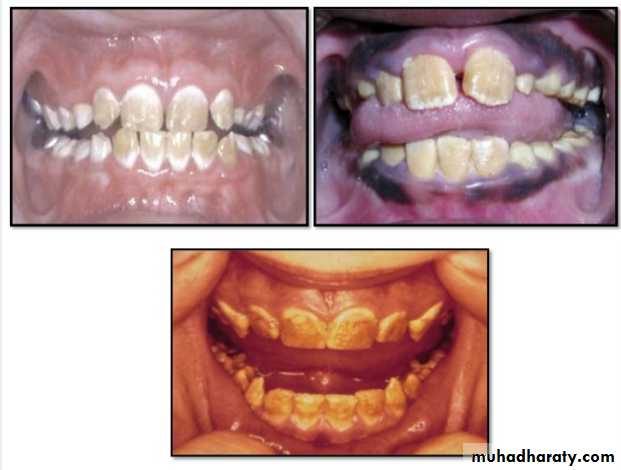

Hypocalcified Amelogenesis Imperfecta:

*Enamel matrix is formed in normal quantity,poorly calcified.

When newly erupted:Enamel is normal in thickness, normal form, but weak , and opaque or chalky in appearance.

With years of function:

Coronal enamel is removed except for cervical portion that is occasionally calcified better.

Radiographically:

Density of enamel & dentin are similar.

• Dentinogenesis Imperfecta: Is an inherited disorder of dentin formation due to autosomal dominant disturbance.

Affects both primary&permanent dentition.

Blue to brown discoloration with distinctive translucence.

Enamel frequently separates easily from underlying defective dentin.

Dentinogenesis Imperfecta(Hereditary Opalascent Dentin)

Bulbous crownsCervical constriction

Thin roots

Early obliteration of roots canals & pulp chambers.

Treatment:

Prevent loss of enamel& subsequent loss of dentin

through attrition.

Cast metal crowns for posterior & jacket crowns for anterior teeth